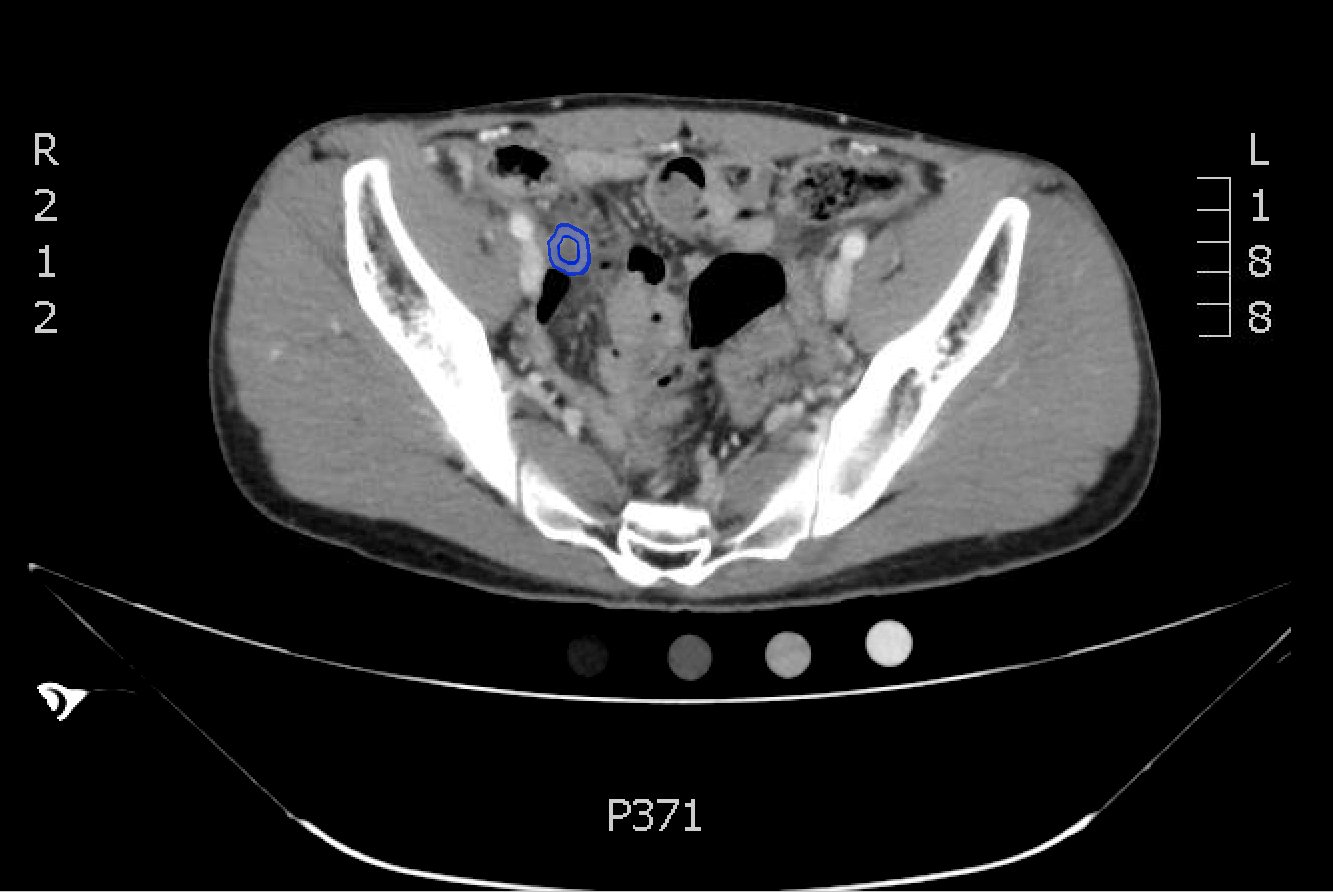

The CT abdomen/pelvis with intravenous contrast shows a dilated appendix (see red outline) with thickened, hyperenhancing wall (see blue outline) best visualized in the axial and coronal planes.